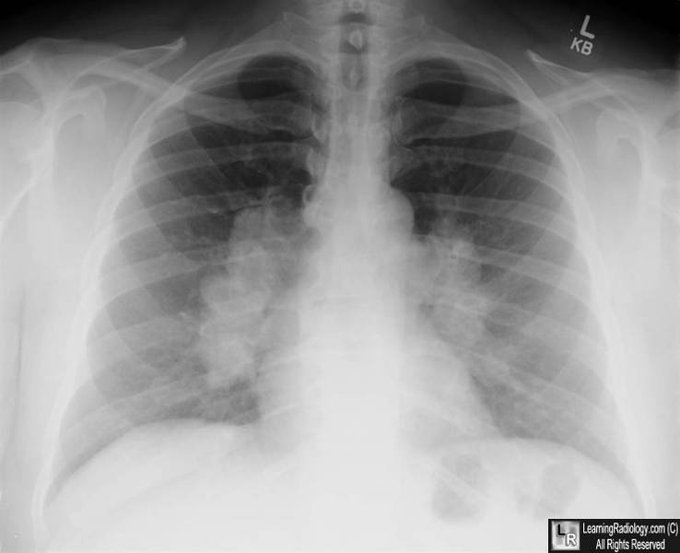

Adenopaties parahiliars bilaterals = Sarcoïdosi

Mentre no es demostri el contrari!